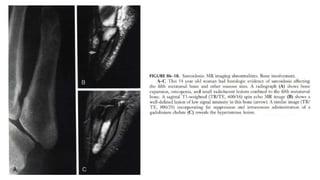

 Musculoskeletal involvement can present as osseous sarcoidosis (axial

manifestation or sacroiliitis) in up to 13% of patients or sarcoid

myopathy in up to 75%, the latter of which is only rarely symptomatic

 Other skeletal areas that may be affected by sarcoidosis include nasal

bones, pelvic girdle structures, ribs, and the skull.

 Lesions in the pelvic bones or in the spine may at first lead one to suspect

cancer metastases.

 Highly probable sarcoid arthritis includes the typical features of the

trabecular pattern, osteolysis, cyst formation, and punched-out lesions